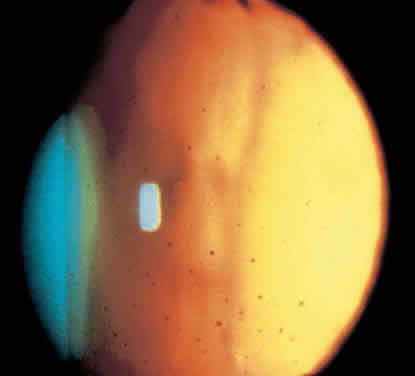

Chandler and Grant described this rare form of inflammatory glaucoma in 1965.98 It presents as open angle glaucoma unresponsive to medical treatment. The eye appears quiet, with minimal anterior chamber cellular reaction and few keratic precipitates. On gonioscopy, multiple broad, flat, clear to yellow precipitates are seen that may be solitary or confluent (Fig. 4). Eventually peripheral anterior synechiae develop in these areas.98 The number and extent of precipitates do not correlate with IOP.98 The disease is usually bilateral and found most commonly in patients older than 50.99 Many cases remain idiopathic, but some patients develop other signs of ocular or systemic inflammation,99 such as sarcoidosis.29 The condition responds well to intensive topical steroids29 and aqueous suppressants, but patients with extensive synechiae may need filtering surgery. Recurrences are common and can be asymptomatic. In one study nine of nine patients experienced recurrent disease, one patient 16 years after the original episode.99 Some patients require chronic suppression with topical steroids or long-term treatment with glaucoma medicines.99

Fig. 4. Gonioscopic view of the iridocorneal angle showing inflammatory precipitates of the trabecular meshwork. (Van Bus-kirk EM: Clinical Atlas of Glaucoma. Philadelphia: WB Saunders, 1986.)